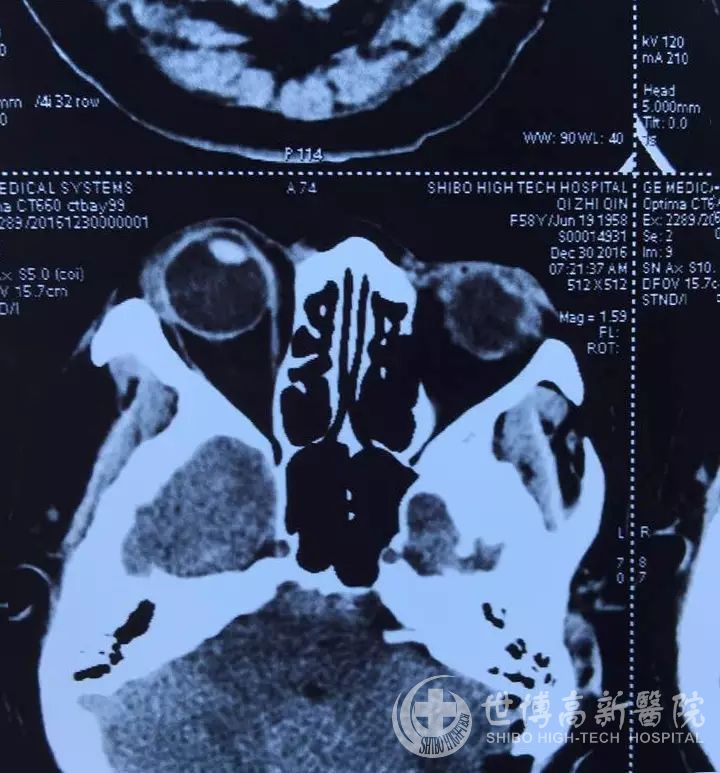

经过检查发现,而导致齐某面部痉挛的主要原因是小脑前下动脉压迫面神经。韦鹏翔教授决定为病人进行微血管减压手术治疗这一顽固性面肌痉挛。

手术由韦鹏翔教授主刀,在相关科室和助手配合下顺利进行,采用乳突后小切口入路。本次手术动用了目前国内最先进的莱卡OH-X手术显微镜,术中脑干、小脑前下动脉、面神经、内听动脉显露清晰,小脑前下动脉压迫面神经。韦鹏翔教授凭借丰富的显微神经外科手术经验,在12倍显微镜下,仔细分离引起面肌痉挛的责任血管及面神经出脑干部位后,将TEFFLON特殊隔离材料植于责任血管及面神经之间,阻断责任血管对面神经的刺激。手术仅耗时3小时余。术后病人即清醒,面神经及相关神经功能无损伤,缠绕病人多年的顽固性面肌痉挛消失。术后影像学资料显示:术野无血,无损伤,隔离材料位置良好,病人治愈,手术达到国内领先水平。